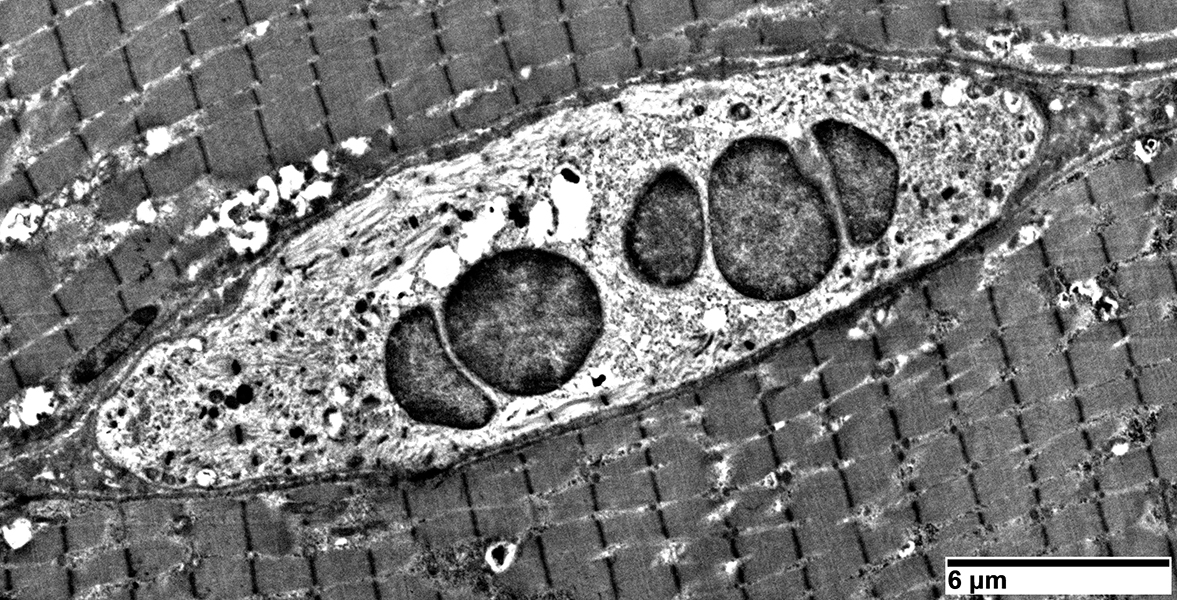

Pyknotic nuclear clumps: Ultrastructure

- Ultrastructure: 1; 2